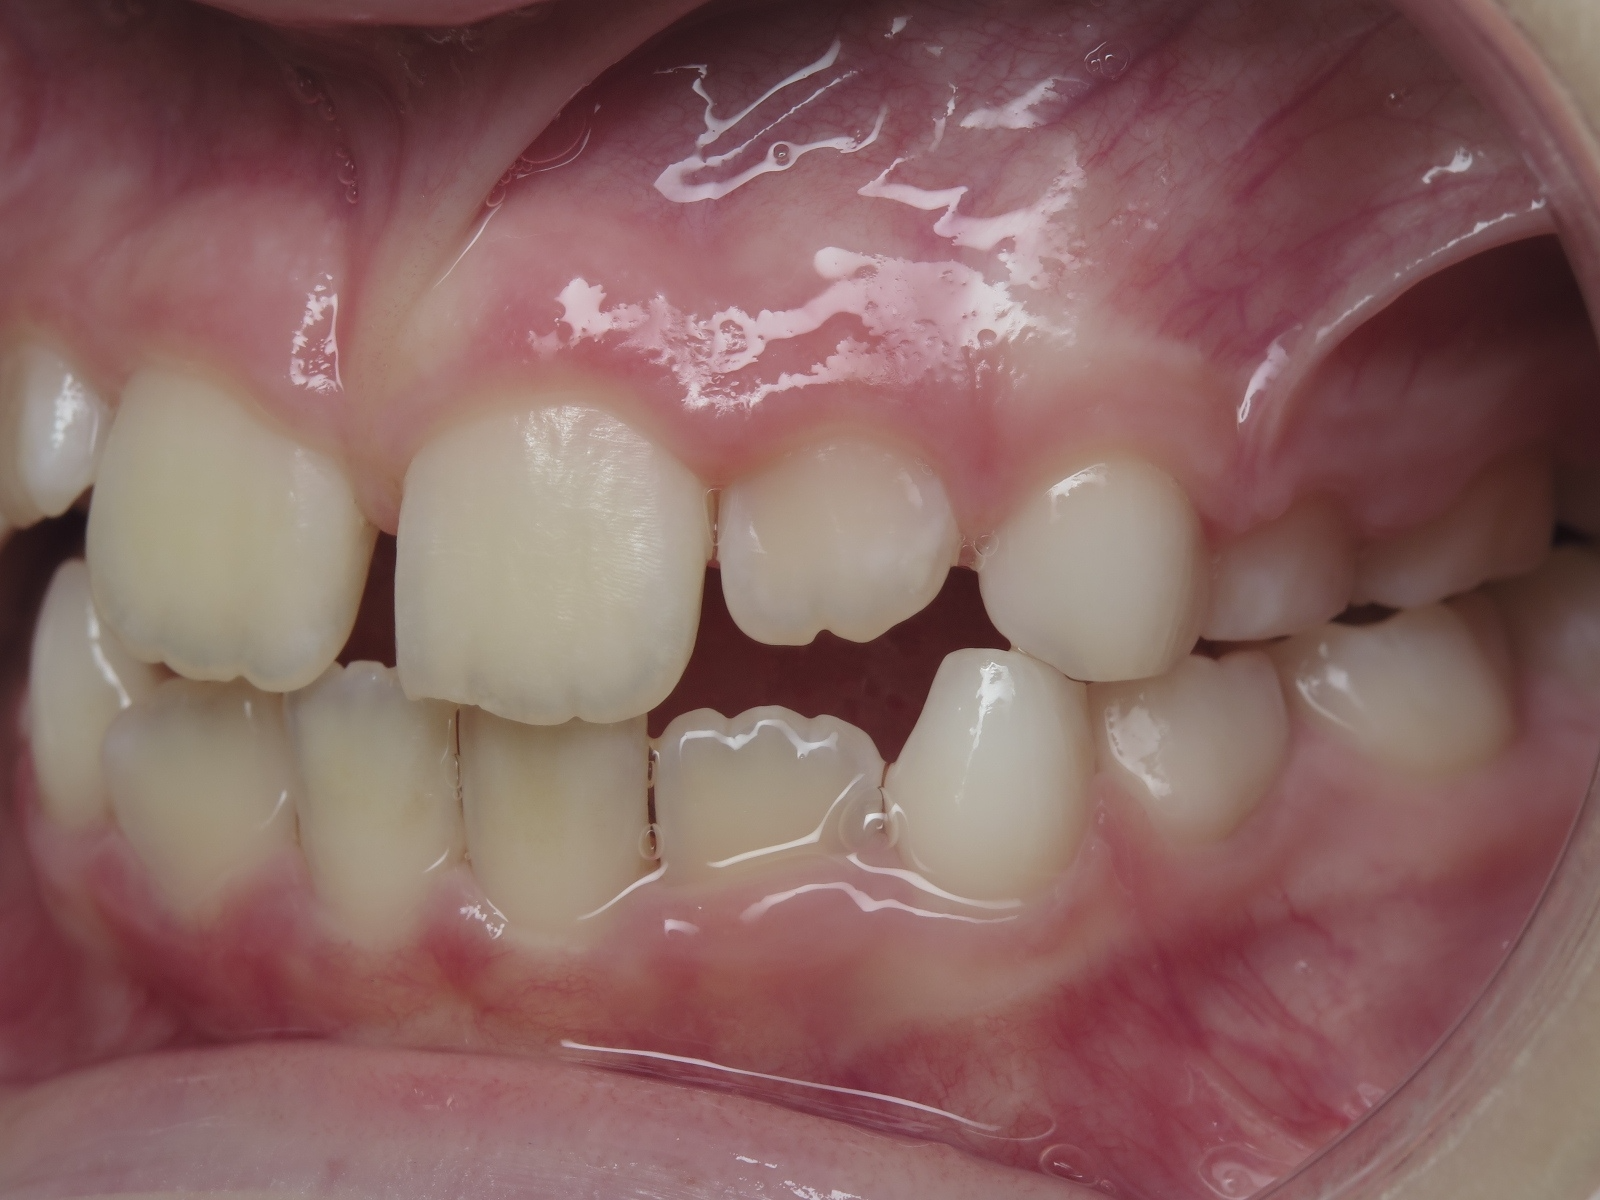

18 béance inversé droit 4 ans

inversion des dents postérieur et espace entre l'arcade du haut et du bas (béance)

surveillance évolution de la dentition

bilan de début et en cours de traitement